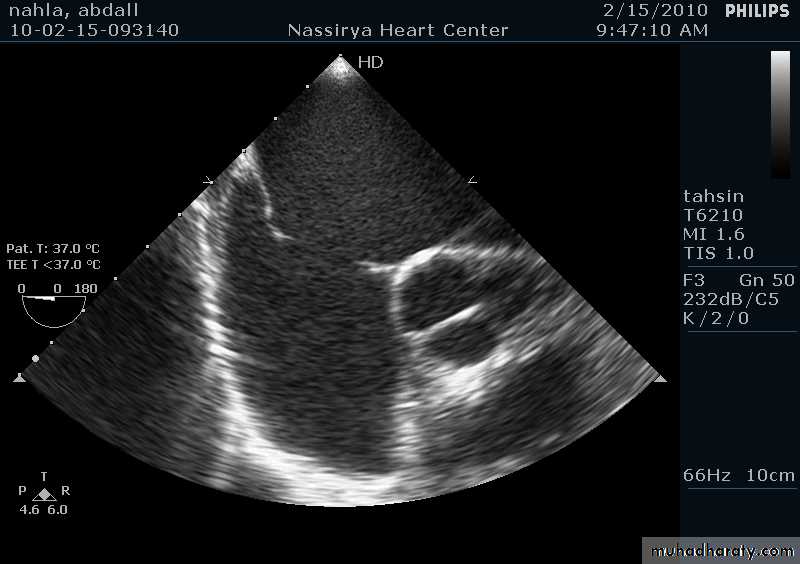

33Echocardiography & TEE

Shows the size of the defectThe direction of blood flow

The pulmonary artery pressure34

Ostium Primum ASD

37

38